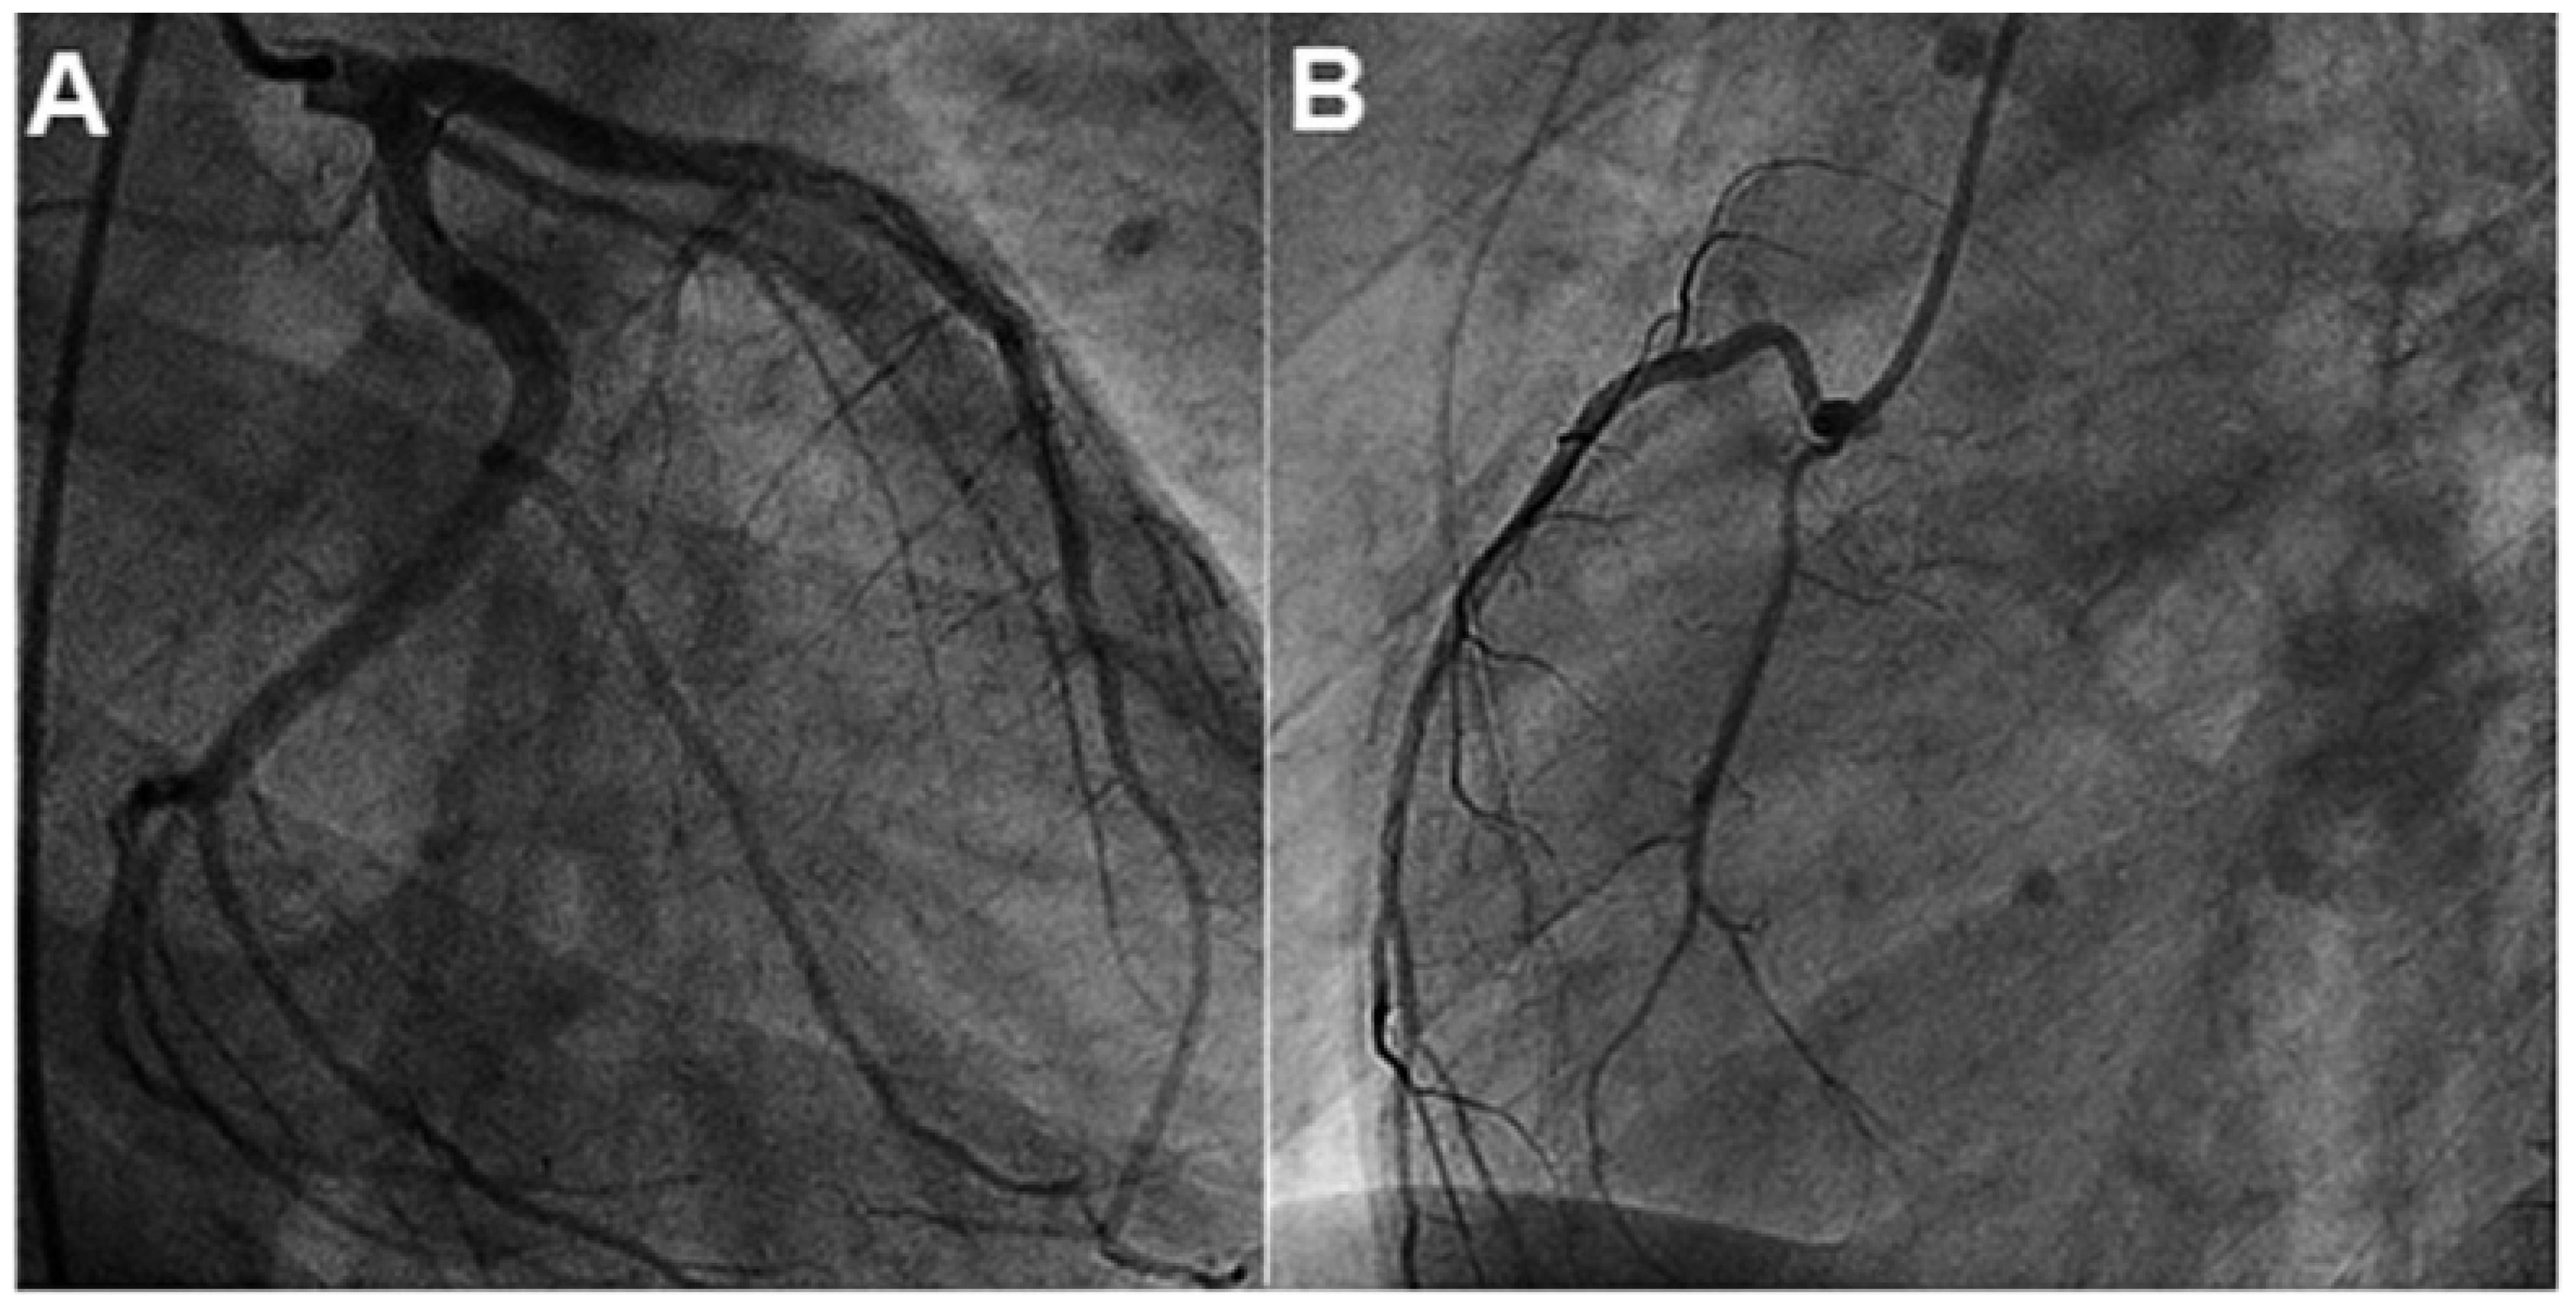

Evaluation of Acute Peri-Myocarditis with Cardiac Magnetic Resonance Imaging

Case report